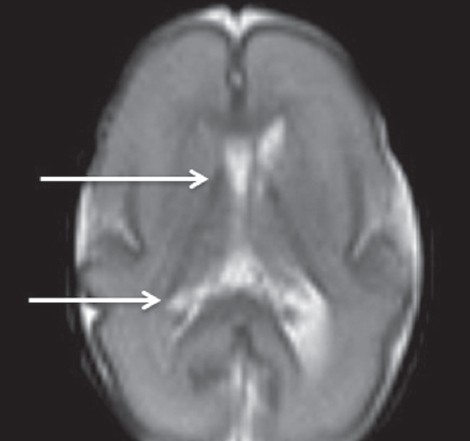

Как видно из таблицы, при выполнении МР-исследования в ПКВ 27–32 недели герминальный матрикс визуализировался у восьми недоношенных детей на ДВИ в виде усиления МР-сигнала вдоль боковых стенок боковых желудочков мозга, а также вдоль передних рогов над хвостатыми ядрами с обеих сторон (рис. 4). На Т2 ВИ герминальный матрикс достоверно выявлен у семи новорожденных (рис. 5). На Т1 ВИ герминальный матрикс достоверно выявлен у двух новорожденных (рис. 6). На последовательностях FLAIR герминальный матрикс не визуализировался.

Рис. 5. МРТ головного мозга недоношенного ребенка (ПКВ 28 недель). Т2 ВИ, аксиальная проекция, стрелками выделены участки герминального матрикса, расположенного вдоль наружных стенок боковых желудочков, гипоинтенсивный МР-сигнал

Fig. 5. MRI of preterm newborn (PCA 28 weeks), Т2-WI, axial plane. Arrows mark the areas of the germinal matrix located along the external walls of the lateral ventricles (hypointense MR signal)

В нашем исследовании герминальный матрикс визуализировался на Т1-импульсной последовательности только у небольшого числа детей (у двух детей) в возрастной группе до 32 недель ПКВ в виде гиперинтенсивного сигнала от нижней стенки переднего отдела боковых желудочков. На Т2 ВИ герминальный матрикс выявляется у большего числа детей (у 7 из 9 детей) в возрастной группе 27–32 недели ПКВ, изменение интенсивности сигнала от герминального матрикса представлено гипоинтенсивным МР-сигналом от передних отделов и наружных стенок тел боковых желудочков. Использовать Т2-импульсную последовательность в оценке церебральной зрелости у недоношенных детей рекомендует S. Counsell [4]. Он отмечает снижение интенсивности Т2-сигнала от латеральных стенок и передних отделов боковых желудочков у недоношенных детей в ПКВ до 32 недель. Как полагает S.J. Counsell, сохранение гипоинтенсивного Т2-сигнала от этих структур у недоношенных детей старше 32 недель ПКВ может свидетельствовать о нарушении глиальной миграции [5].